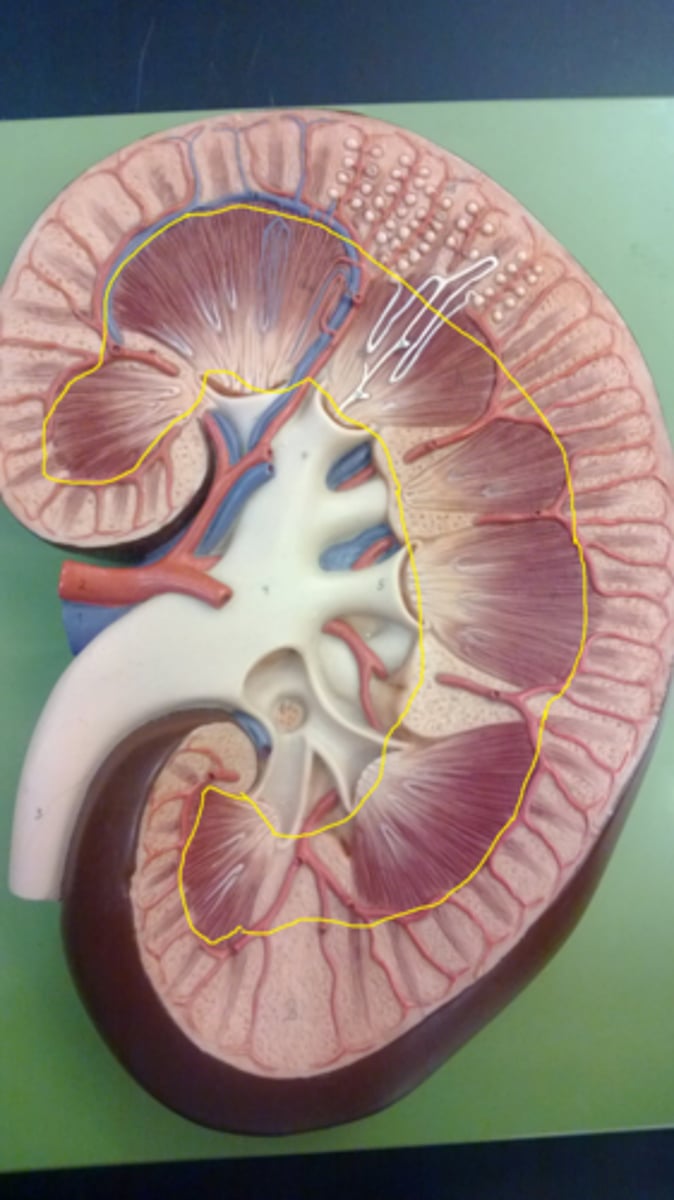

renal pyramids

striated triangular-shaped areas of tissue in the medulla of the kidney

renal columns

extensions of cortex in between pyramids

minor calyx

cup that nestles the papilla of each pyramid; collects its urine

major calyx

urine passageway

renal pelvis

central collecting region in the kidney